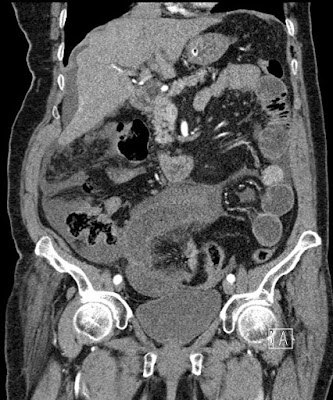

Organoaxial cecal volvulus

Coronal reformatted CT: dilated cecum  in the left upper quadrant of the abdomen. The cecum is displacing the stomach superiorly. Obstructed small bowel.whirl-sign according to the twisted cecum (organoaxial form)2100812011.11.01.lásd...